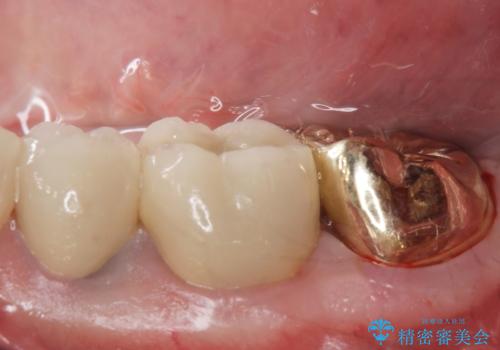

ゴールドクラウン

- 過去に治療したゴールドの詰め物が取れて来院。取れたのは2回目だそうです。レントゲンでは適合が良いので再装着可能だったが、

もう取れたくないとの事だったので被せ物のご案内をしました。ゴールドの被せ物の希望だったのでゴールドクラウンでの治療になりました。

適合の良いゴールドクラウンが入りました。

ゴールドは適合が良く、割れる心配もありません。

また、虫歯になるリスクも銀歯と比べて低くなります。